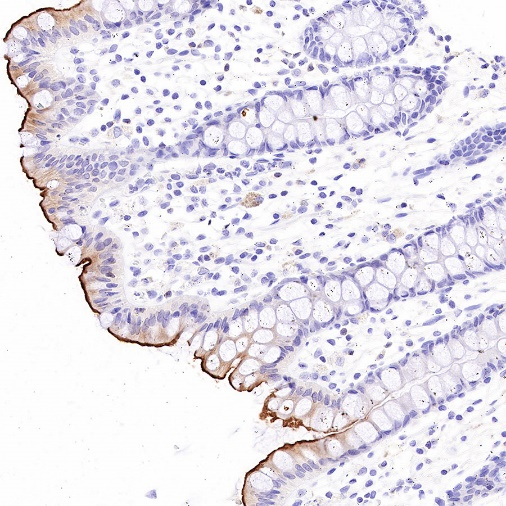

Immunohistochemistry

IHC shows positive staining in paraffin-embedded human kidney. Anti-MDR1/ABCB1 antibody was used at 1/1000 dilution, followed by a HRP Polymer for Mouse & Rabbit IgG (ready to use). Counterstained with hematoxylin. Heat mediated antigen retrieval with Tris/EDTA buffer pH9.0 was performed before commencing with IHC staining protocol.